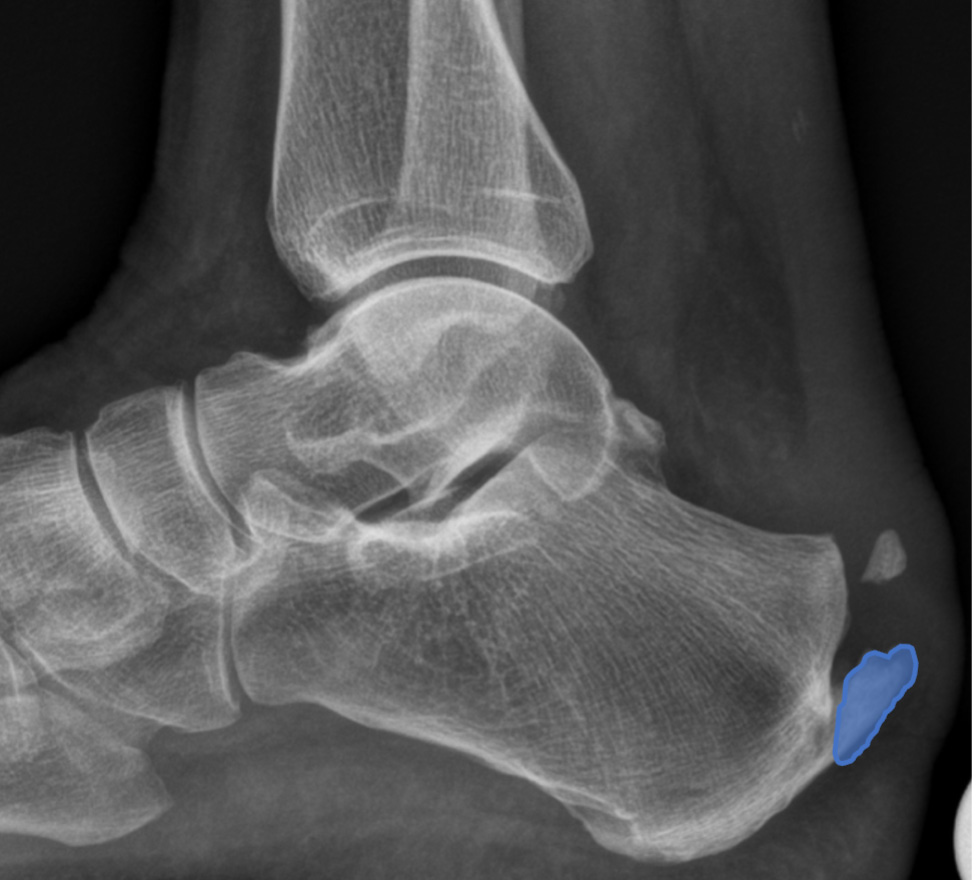

Die Achillessehne ist täglich starken Belastungen ausgesetzt. Unterschieden wird zwischen der häufigeren Form der Achillessehnenentzündung in der Mitte der Sehne und einer Entzündung am Sehnenansatz (Enthese) am Fersenbein. Letztere kann zu einer Verknöcherung des Achillessehnenansatzes und damit zu einem oberen (dorsalen) Fersensporn führen *. Eine Sonderform stellt die Entzündung der Achillessehne mit einer Reizung des Schleimbeutels durch einen herausstehenden Teil des Fersenbeins (Haglund-Deformität) dar, der bei Bewegung des Fusses nach oben gegen die Achillessehne drückt und diese reizt.

Der Ansatz der Achillessehne ist hohen mechanischen Kräften ausgesetzt, weil die Kraft von der elastischen Sehne auf den viel härteren Knochen übertragen werden muss *, *, *. Der Sehnenansatz ist vergleichbar mit dem Übergang eines Kabels in einen Stecker. Wird der Bereich zu stark belastet, kann das Übergangsgewebe verknöchern.

Die Haglund-Deformität ist ein vergrösserter Knochen am Fersenbein nahe des Achillessehnenansatzes, der zu einer Reizung und Entzündung des Schleimbeutels zwischen der Achillessehne und des Knochens führen kann. Dabei kann auch die Achillessehne geschädigt werden *.

Diagnose

Ein Fersensporn zeigt sich als kleine, spitze Verhärtung am Ansatz der Achillessehne. Auf einem Röntgenbild sind die knöchernen Veränderungen gut zu erkennen. Zur Beurteilung der Vernarbung und Entzündung ist womöglich eine Magnetresonanztomographie (MRT bzw. engl. MRI für magnetic resonance imaging) oder eine Ultraschalluntersuchung erforderlich.